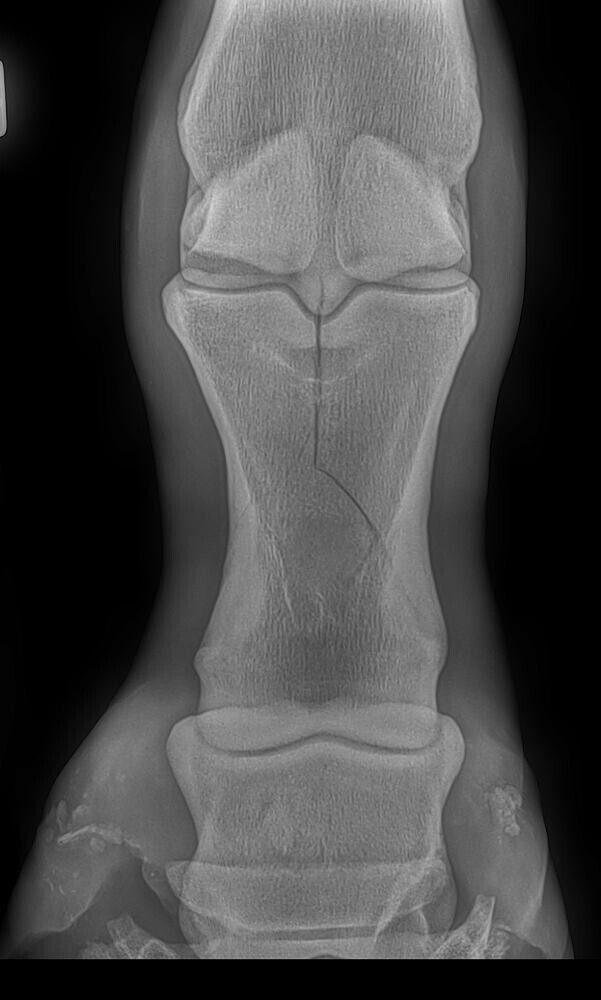

The repair of the fracture shown in Figure 2 was performed on a standing horse. The finished repair is in Figure 3. Figure 4 shows standing screw placement into a knee fracture.